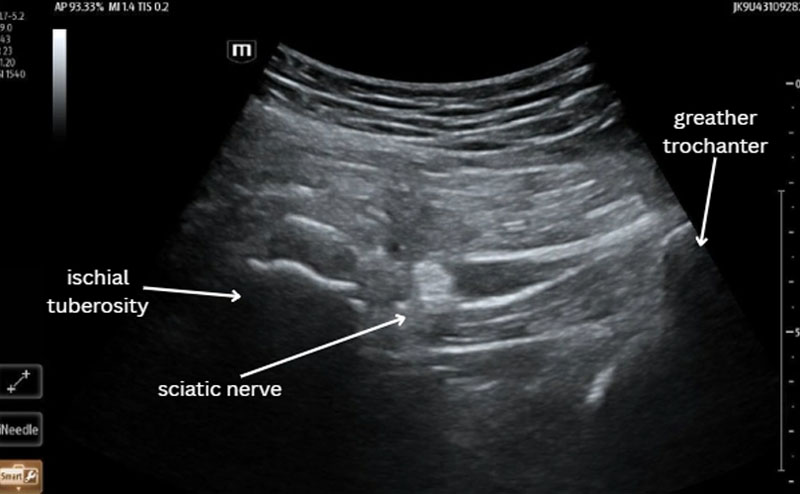

Ultrasound-guided Transgluteal Sciatic Nerve Hydrodissection (TSNH) is a similar procedure wherein D5W or a similarly inactive fluid is used to decompress the sciatic nerve. [Figure 1] This procedure causes mechanical decompression and does not cause motor blockade; it is therefore useful in the ED as patients are ambulatory after the procedure and can be safely discharged with their pain controlled. Here we present a case of a patient in the ED presenting with sciatic pain treated with this procedure.

A 61-year-old male presented to the ED complaining of 2 weeks of persistent worsening right-sided back pain radiating down his right leg to his foot. He also reported numbness to his medial calf and difficulty ambulating with a walker. Pain was unrelieved by tylenol, ibuprofen, or muscle relaxants. Consent for a TSNH was obtained and the procedure was performed under ultrasound guidance using sterile technique with a 20 gauge echogenic nerve block needle. 20mL of D5W was used for hydrodissection. The patient was placed in lateral recumbent position and the anatomy was identified. [Figure 1] The needle was visualized using a longitudinal approach and D5W was deposited around the sciatic nerve. [Video 1] The patient reported improvement in his pain scale from a 10 to a 4, became ambulatory, and was discharged an hour later without complications.